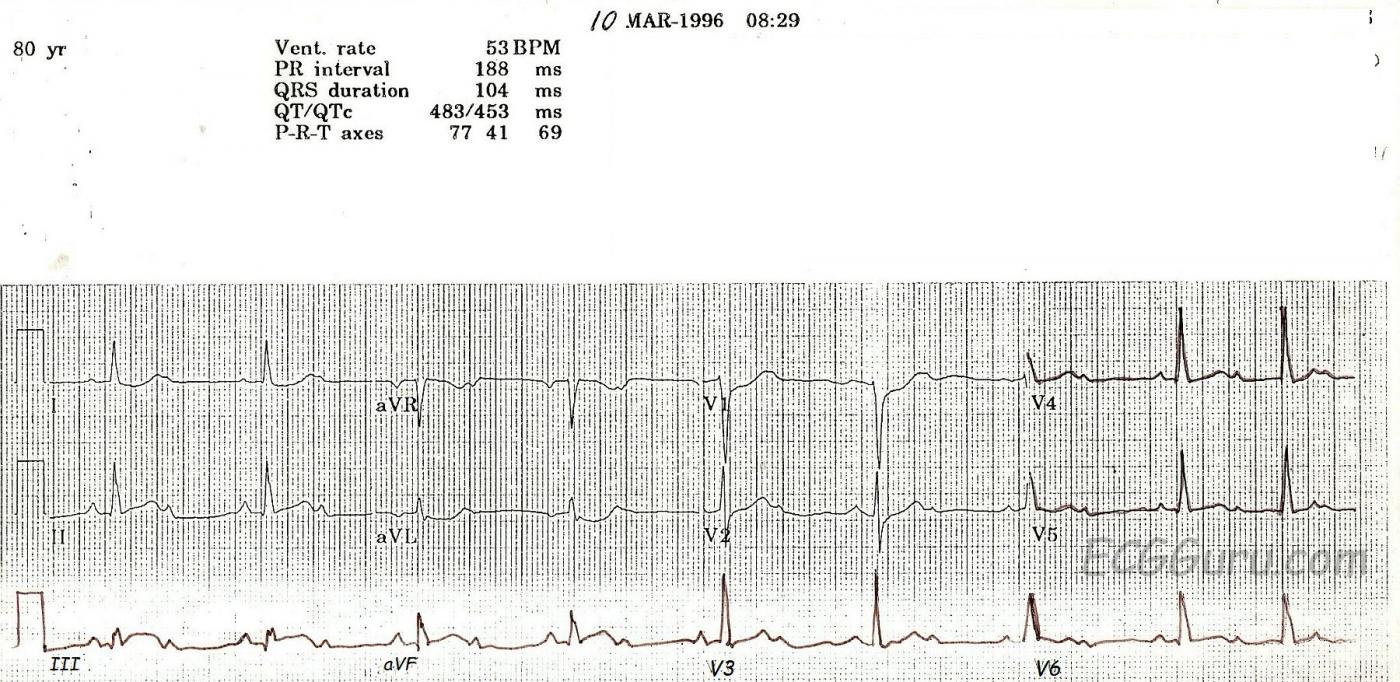

This ECG is from an 80-year-old woman who had an acute inferior wall M.I. with a second-degree AV block.

This is a good example of a Type I, or Wenckebach, block which is initially conducting 2:1. At the end of the ECG, two consecutive p waves conduct, showing the "progressively-prolonging PR interval" hallmark of a Type I block. Type I blocks are supraHisian - at the level of the AV node - and generally not life-threatening. Blocks that are conducting 2:1 present a danger, however, in the effect they have on the rate. Whatever the underlying rhythm is, the 2:1 block will cut the rate in half! This patient has an underlying sinus tachycardia at 106, so her block has caused a rate of 53. In light of her acute M.I., that rate is probably preferable to the sinus tach. This patient’s BP remained stable, and she did not require pacing.

The ST signs of acute M.I. are rather subtle here. Note the "coving upward" shape in Lead III, and the reciprocal depressions in I, aVL, V1, and V2. Type I blocks are common in inferior wall M.I., since the AV node and the inferior wall often share a blood supply - the right coronary artery.

While the print quality of this ECG is not the best, it is a great teaching ECG because it starts out with 2:1 conduction, then at the end of the strip, proves itself to be a Wenckebach block.

Another tell-tale sign that this 2:1 block is really a Mobitz I is the narrow QRS complex. A Mobitz II block is really a bifascicular block that is intermittently blocking in the third fascicle creating a momentary third degree block (hence the need for an emergent pacemaker insertion). So a Mobitz II block is virtually always in the presence of a wide QRS complex. Certainly, a Mobitz I block can occur in the presence of a pre-existing bundle branch block, but that doesn't happen very often. On the other hand, a Mobitz II block with a narrow QRS complex would be very unusual indeed.

Although this ECG is an exception, Mobitz I block is very, very frequently accompanied by a baseline first degree AV block.

The other issue relates to the acute inferior infarction. On many occasions, the ST deviation in the inferior leads is very subtle or simply not there. But ST depression in lead aVL is almost diagnostic of inferior wall MI. Certainly, LBBB and LVH can cause ST depression in aVL, but aside from those two entities, the next most common cause would be a reciprocal change during an inferior MI (in the context of a patient with symptoms compatible with ACS). The reciprocal change of ST depression in aVL very often appears well before the STE in the inferior leads.